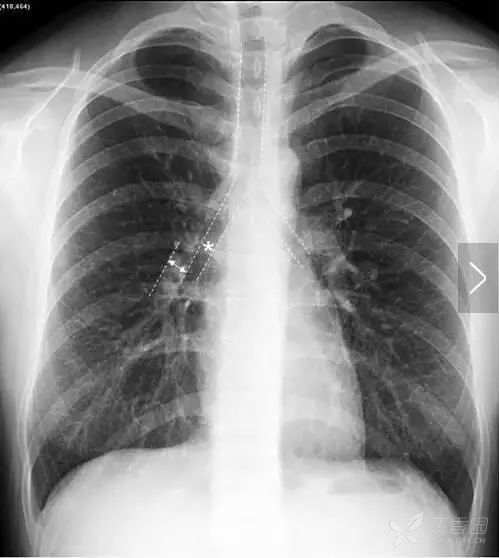

右肺门上下部分形成一钝角叫右肺门角(图9),右肺门处病理策划的出现可以导致右肺门角消失。右肺门下半部分主要是右下肺动脉干(图10)。

图10 右下肺动脉干(双向箭头标示的宽度)在含有气体的中间段支气管的衬托下显示清楚,正常情况下右下肺动脉宽度通常<15 mm。